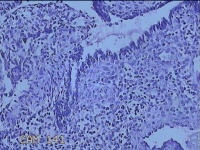

宫腔内容物

性别

女

年龄

47岁

临床诊断

1.异常子宫出血 2.慢性宫颈炎

一般病史

不规则阴道流血21天。

标本名称

大体所见

灰白暗红色不规则碎组织2.5x1.8x0.3cm一堆。

图4